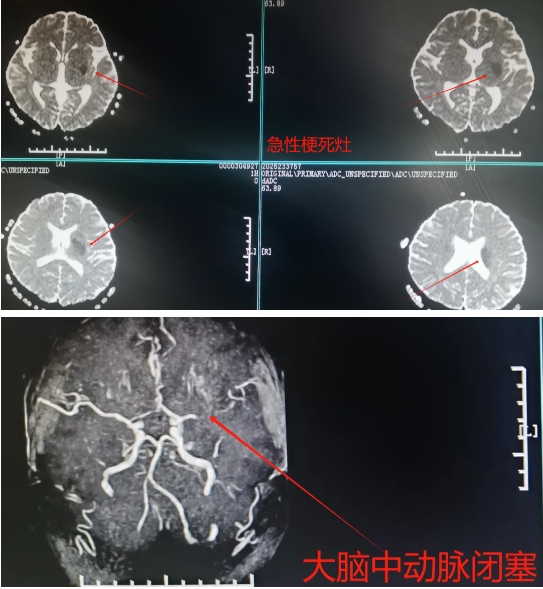

“刚才还在玩手机,怎么突然动不了、说不出话了?”18岁河南大学生小马(化名)的遭遇,把所有人都吓出一身冷汗。原来,小马右侧肢体偏瘫、说不出话,短短3小时,这个原本生龙活虎的年轻人,竟被死神掐住了咽喉——急性脑梗死,左侧大脑中动脉完全闭塞!